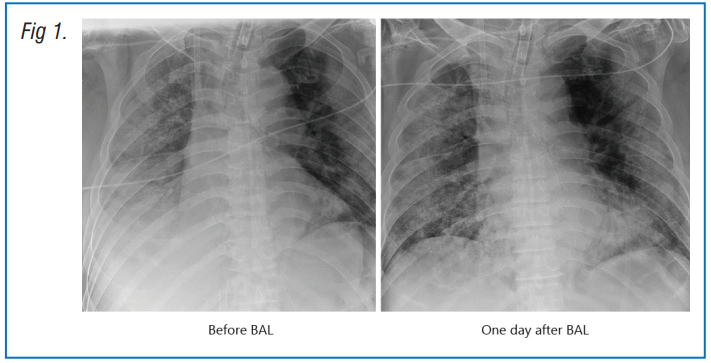

Male patient, aged 66 years was admitted to hospital presenting with cough and fever for 10 days. He had COPD and hypertension. The patient was intubated and ventilated following progressive hypoxemic respiratory failure despite high-flow nasal oxygen therapy (HFNO). Veno-venous ECMO was instituted on day 2 due to refractory severe acute respiratory distress syndrome (SARDS). Chest radiography demonstrated worsening opacification in the right low zone. Hence, bronchoscopy was performed on day 4. Therapeutic BAL was performed in the right lower lobe basal segments. A large quantity of mucus was cleared. A chest X-ray the following day showed clearing of the lung fields and restored visibility of the right hemidiaphragm. (Fig 1)